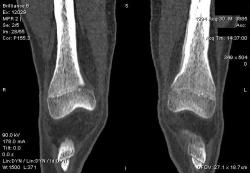

Мальчик 15 лет. Несколько месяцев назад начали беспокоить боли в коленных суставах. Травмы не было. Ребёнку был выставлен диагноз: болезнь Шлаттера, назначено лечение. На фоне лечения отмечалось значительное усиление болей, боли локализовались в левом коленном суставе. При дообследовании выявлена следующая рентгенологическая картина. Наши рентгенологи настаивают на срастающемся переломе. Но: 1) перелом без травмы? 2) бедро так не ломается

В голову приходит остеомиелит или опухоль.

Линейный периостит, уже должен был рентгенологов насторожить.

Локальный гиперостоз, выраженный болевой синдром, структура губчатого вещества диафиза не изменена наводит только на остеойд-остеому.

Я бы на первое место поставила патологическую перестройку, так называемый, стрессовый перелом. Мальчик чем-нибудь занимается?

Согласна с Ola-la - рентгенологическая картина более всего соответствует стрессорному перелому, хотя для него характерна локализация в б/берцовой кости. Меня однако, смущает и настораживает клиника - это как раз тот случай, когда я бы не дала 100% гарантии, что так не может манифестировать остеосаркома... Поскольку другие методы (МРТ, сцинтиграфия) вряд ли помогут, я бы взяла пациента на короткое ( 2недели - месяц) динамическое наблюдение.

Да, на мой взгляд, состояние после обычного "травматического перелома" (трещина), не думаю, что имел место "патологический перелом", так как костная ткань "патологически изменена" минимально. "Перистальная реакция"локальная тоже есть, на КТ "локальная  зона склероза" - все это свидетельствует именно об этом. Хотя в памяти у меня хорошо отложился Ваш последний случай о локальном утолщении кортикального слоя, когда "яйца в гнезде" еще не было. То, что анамнестически "травмы не было" - ничего не значит. Вы, по всей видимости, тоже часто встречались с такими случаями, когда ребенок не акцентировал внимание на "травме", как таковой, хотя клиника есть, боль есть. Конечно, рентгенограммы - не дай бог - ни скиалогии, ни структуры.